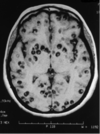

This is the CT of your patient.

What causes it?

What may you find on LP?

What is the treatment?

Cysticercosis

T. solium

CSF with increased lymphocytes and eosinophils

albendazole